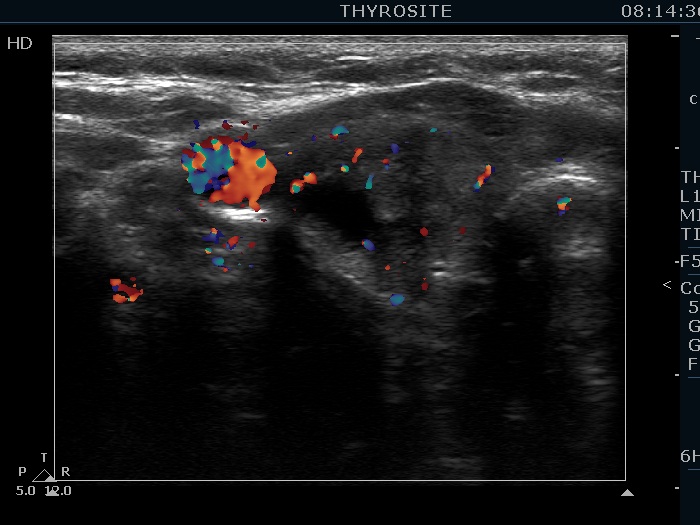

Ethanol sclerotherapy: toxic nodules - Case 2

Two years after repeated therapy (ultrasonographic picture 3)

Right lobe, longitudinal scan, color Doppler mode. The vascularization is not specific.